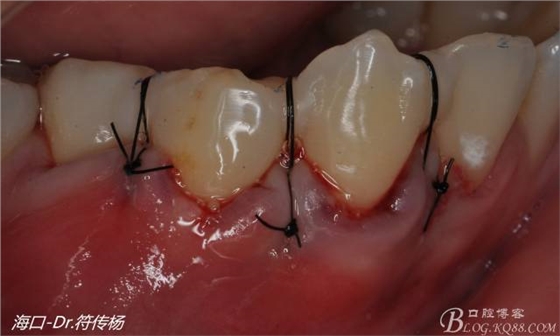

受植區(qū)建議使用雙交叉垂直懸吊縫合術(shù)來(lái)固定結(jié)締組織并能讓齦瓣更貼合根面利于術(shù)后一期愈合

術(shù)后十天牙齦一期愈合